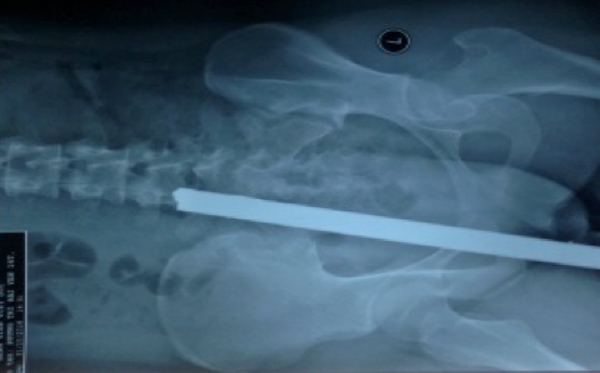

| Nạn nhân được chuyển vào bệnh viện với thanh sắt cắm dài phía sau |

Khi vào viện, nạn nhân vẫn tỉnh táo, huyết áp ổn định, thanh kim loại chọc vào nếp mông lộ ra ngoài khoảng 15cm.

| Cú tông mạnh khiến thanh sắt xuyên sâu |